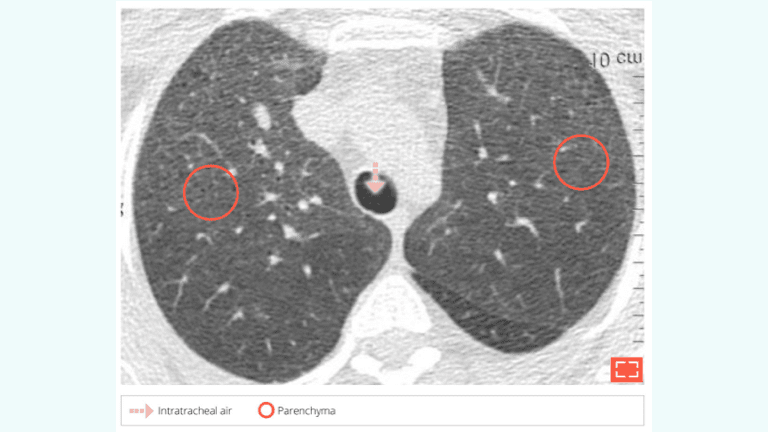

5. Ground-glass opacity with “Dark bronchus sign”

• Diagnosing diffuse ground-glass opacity can be difficult given the homogeneous increase in pulmonary density.

• Diagnosis then relies on comparisons of the intratracheal and bronchial air density (appearing black) and the parenchyma (appearing light grey).

• A gradient that is too significant compared to what is normally observed leads to identification of a dark bronchus sign, indicating a diffuse abnormal opacity of the parenchyma. Unfortunately, this assessment is qualitative, not quantitative.